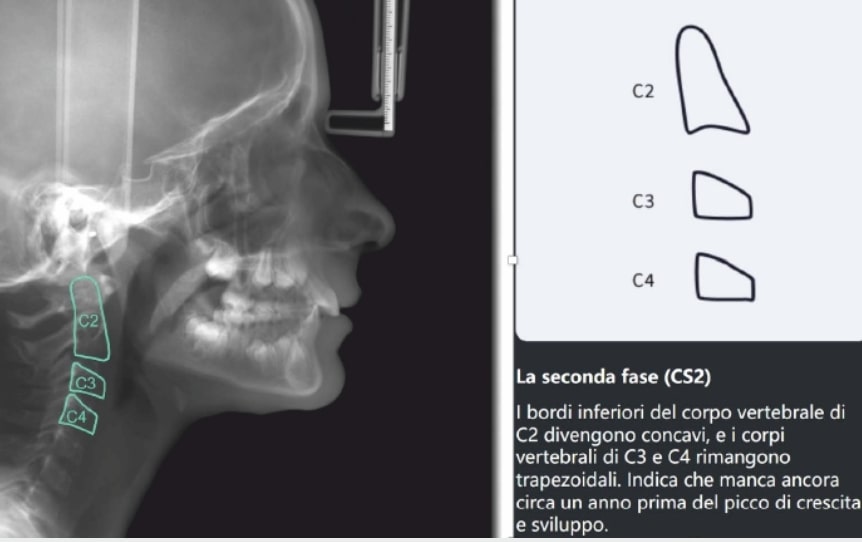

Age: 10 years old

SKELETAL PATERN: Class 2

Treatment plan

Step 1:

- Upper Archform enlargement (dental expansion)

- Normalize Overjet/Overbite (Lower Posterior Extrusion)

- Alignment/Leveling Both Arches

Step 2:

- Mandibular Advancement (A6 protocol) + angelBuon for Class 2 Elastics (Night Time)